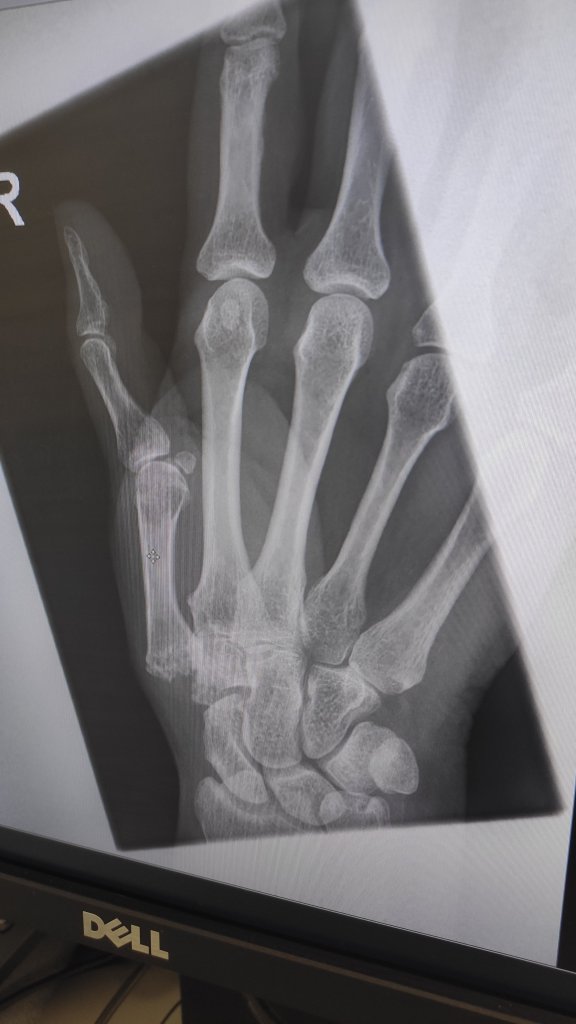

Good news the bone is healing nicely, so the splint is no longer needed. Exercise wise I’m doing all I need to do. We had a discussion over the Right hand though, we had planned the exact same surgery for this side. However the bone stock isn’t there, and it’s far more complex as it involves more joints. They are thinking of a silicon implant and pin. And not do the middle finger at the same time as previously planned, as the thumb is complex enough without adding more.

Next appointment is Sept and by then the consultant will have had another meeting of colleagues to discuss the final plans for the right hand. Curse of Ehlers Danlos Syndrome isn’t it.